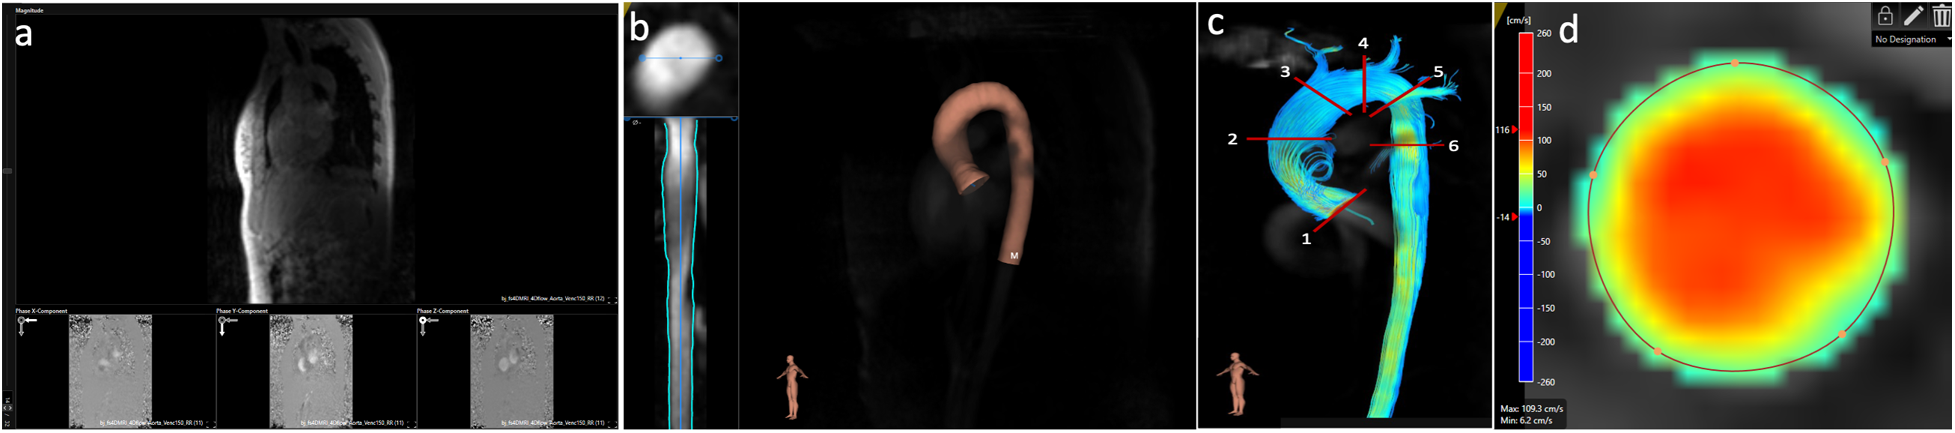

Figure 1

Post-processing of 4D flow CMR data using software 1. (a) Aliasing and background phase offset correction. (b) Placement of the vessel centerline along the thoracic aorta. (c) Positioning of the six analysis planes. (d) Manual correction of the lumen contour in every cardiac phase using a velocity mask overlay beside the magnitude images.